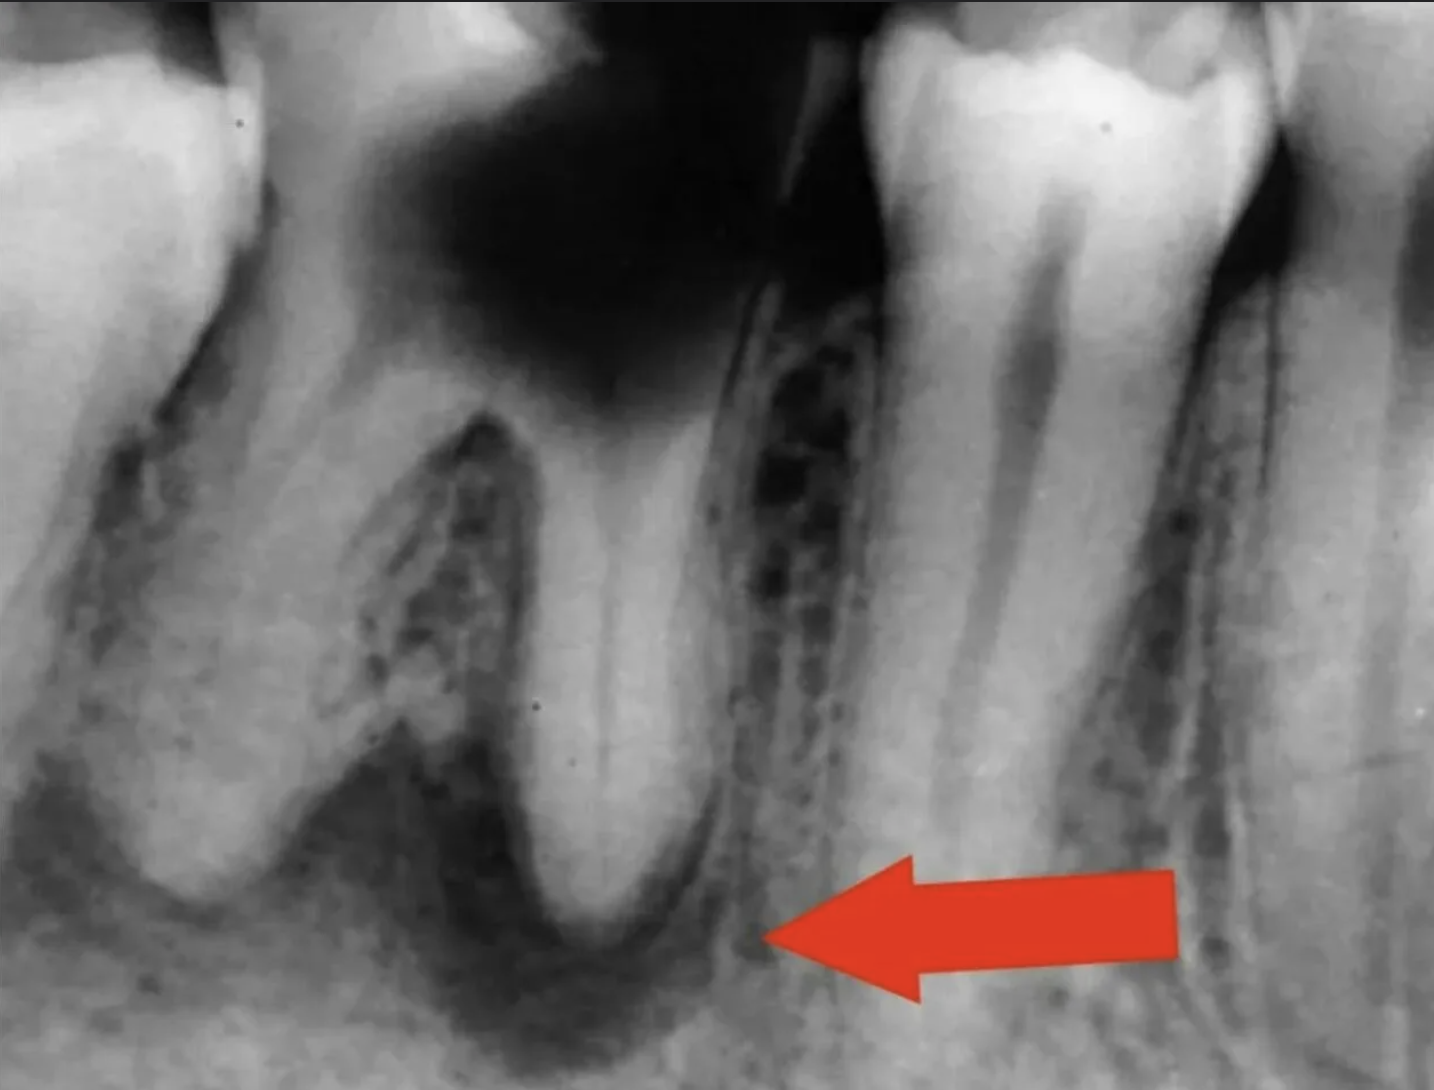

3. Периодонтит: воспалительный процесс в области корня зуба, вызванный инфекцией. Лечение периодонтита может быть сложным и дорогостоящим, поэтому удаление зуба может быть лучшим вариантом.

передонтит зуба мудрости